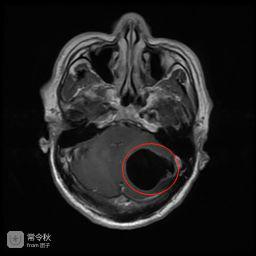

X光片显示,左小腿和右小腿分布着零散的囊虫,头部MR进一步显示,小脑半球内已聚集形成了一个较大的囊性占位……

看着这些触目惊心的图片,刘宇(化名)觉得头脑发麻,没想到自己身上有这么多囊虫在潜伏。

↑(术前头部MR,左侧小脑半球内一较大的囊性占位,压迫小脑、脑干,为囊虫病变。“黑色空洞”部分即为囊虫病灶)

据广东三九脑科医院神经外六科主任吴杰介绍,患者的影像检查提示颅内多发占位病变,结合病史,考虑为颅内多发脑囊虫病,于是为刘宇进行了“左侧小脑囊虫占位切除术”。术后病理提示为脑囊虫病。